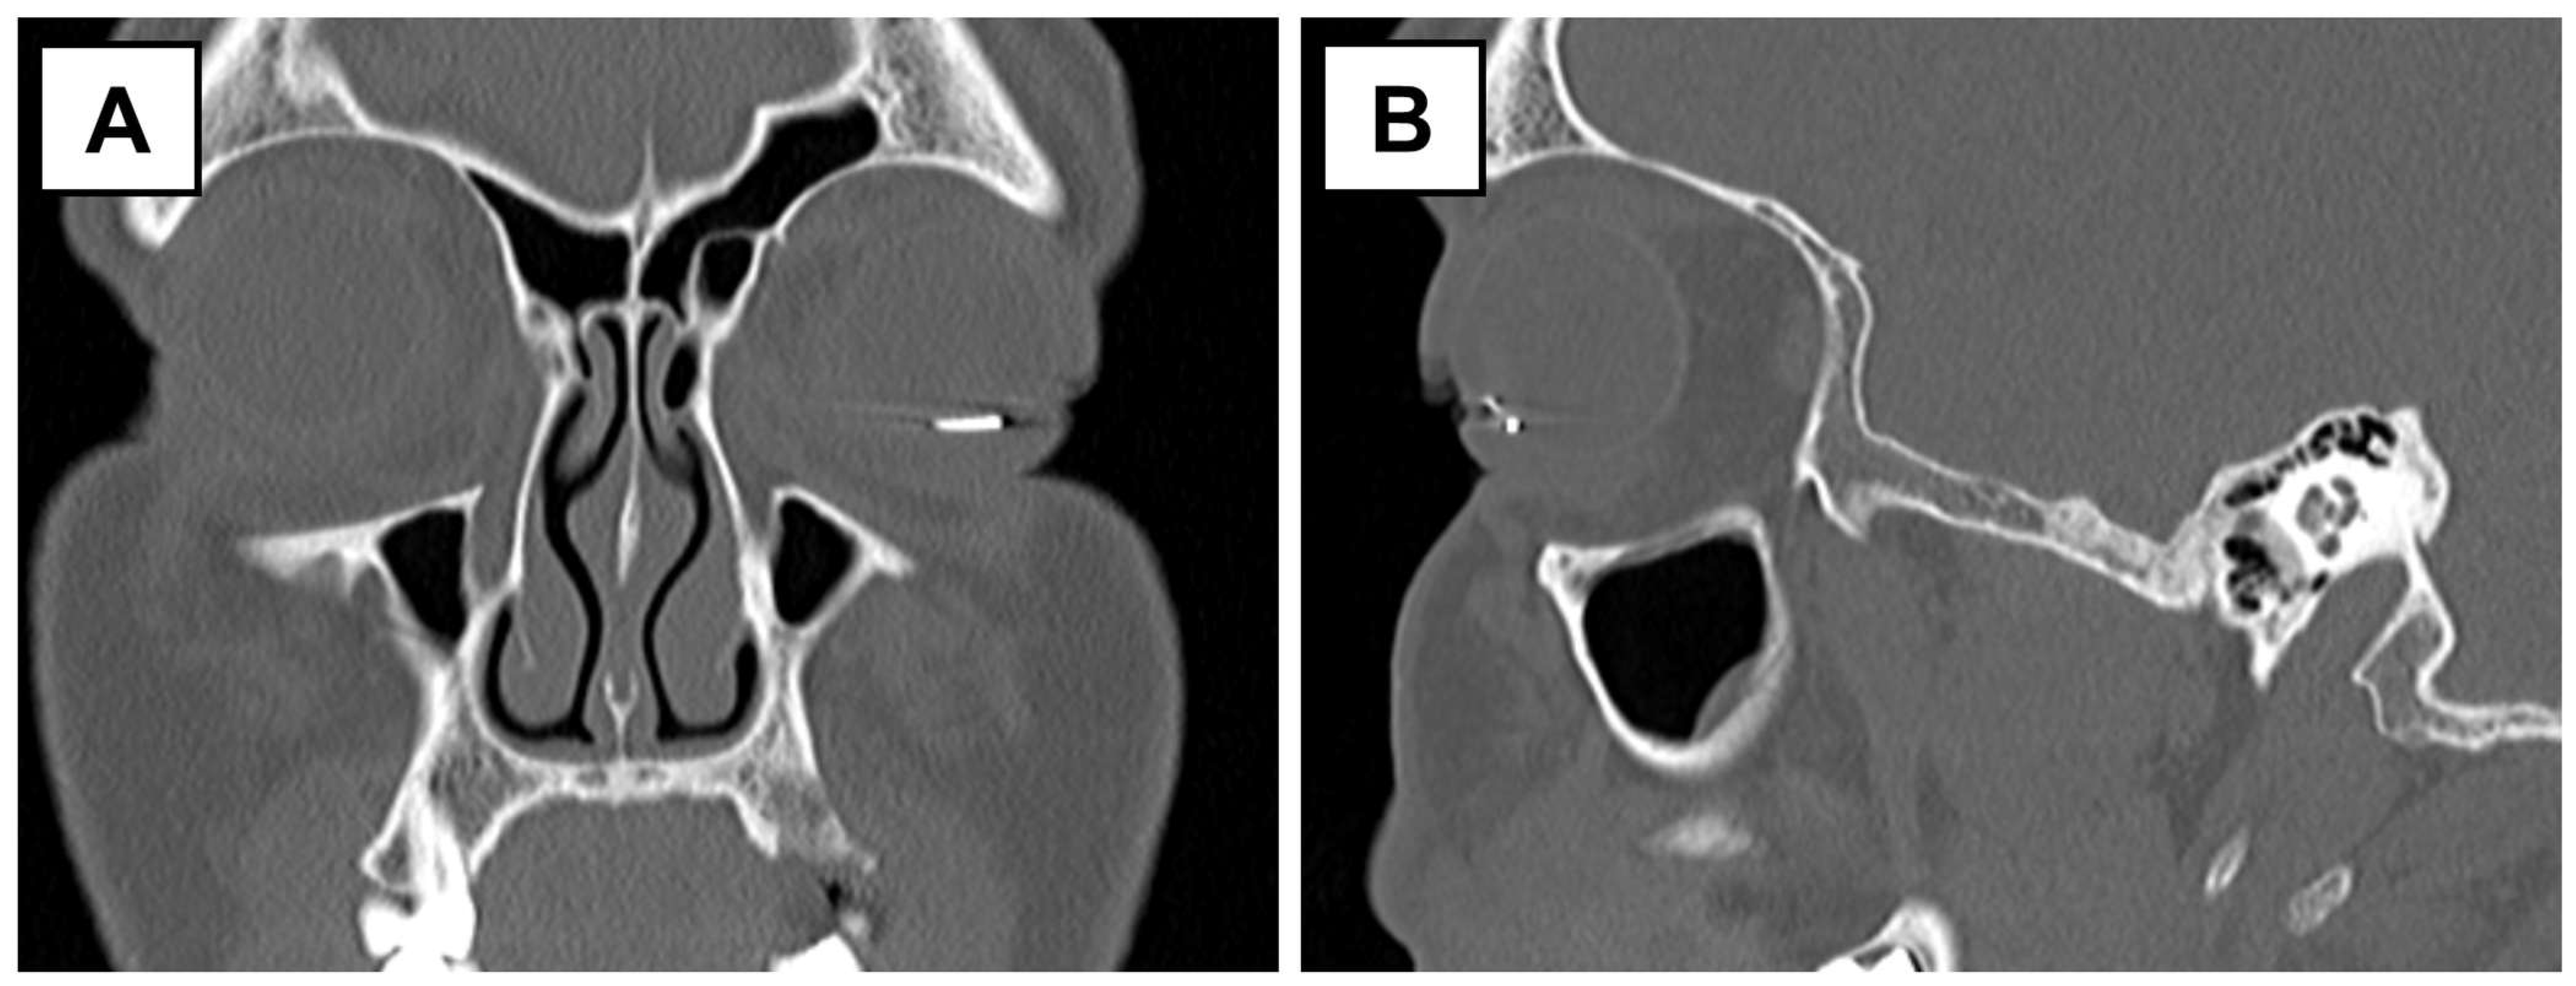

Figure 2.

CT scan of the orbit in the coronal (A) and sagittal (B) views demonstrates a hyperintense signal corresponding to the metallic foreign body in the anterior segment of the left eye.